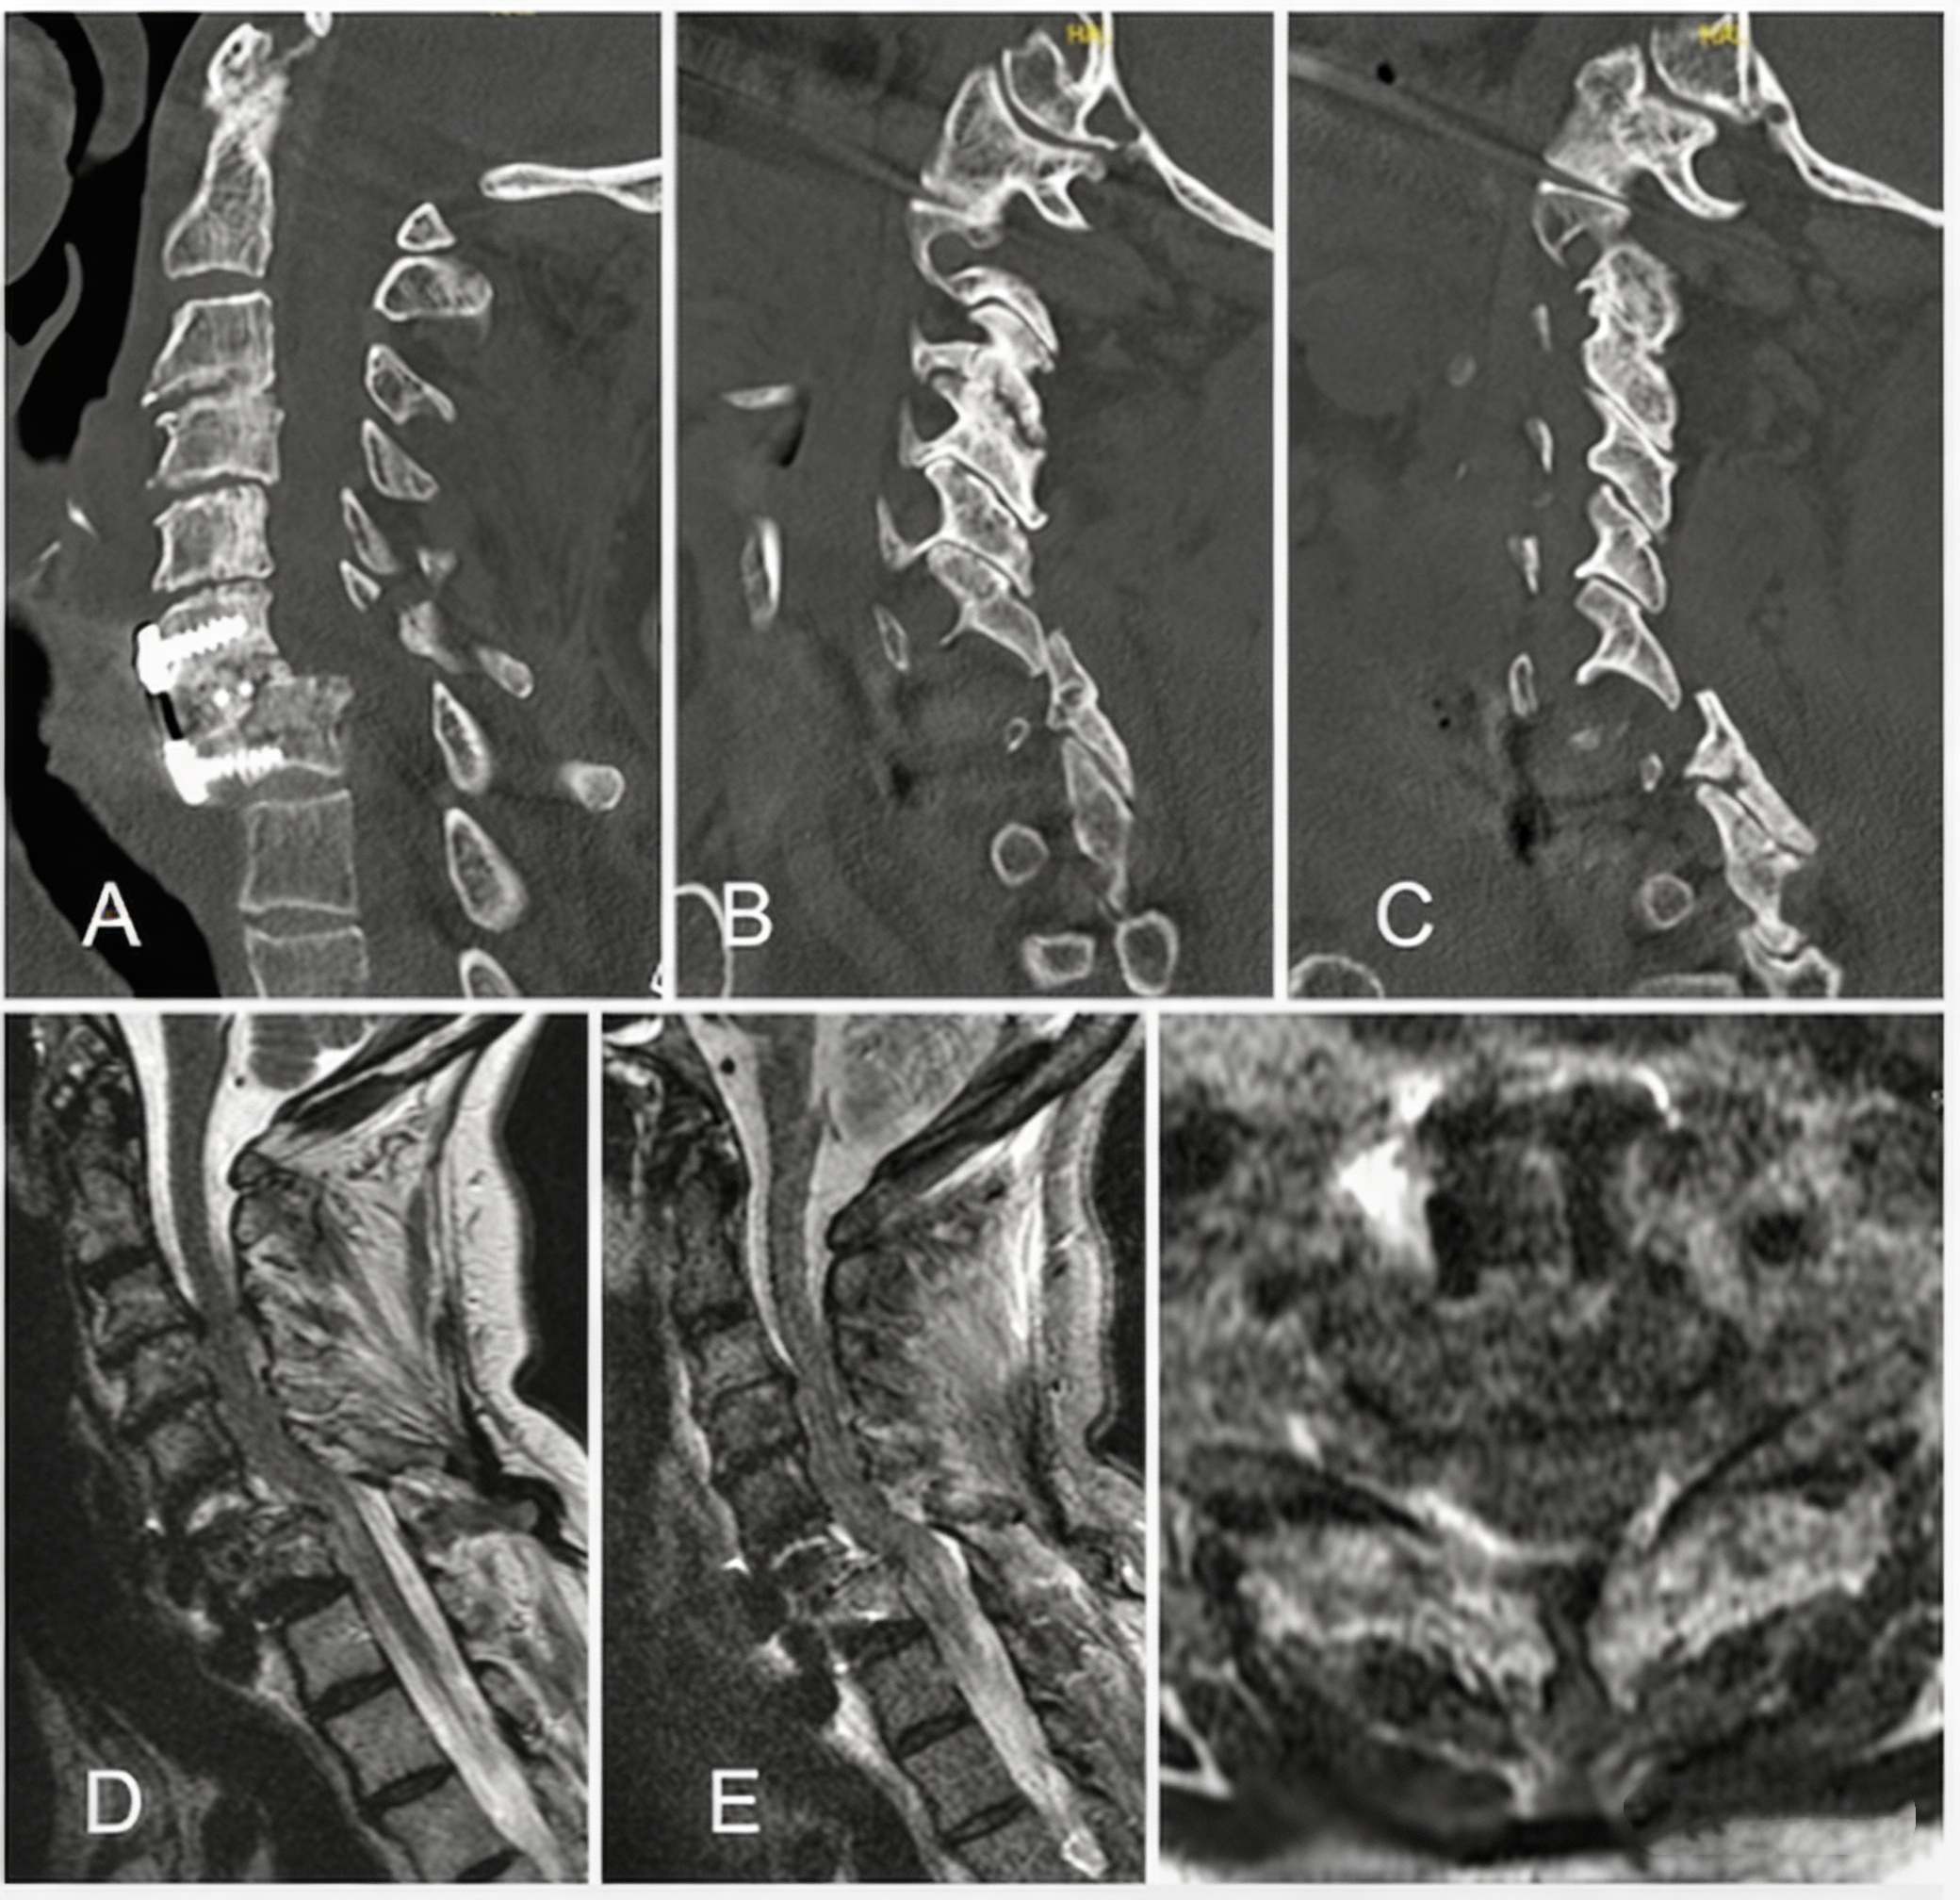

2_副本.jpg

Initial diagnostic CT and MRI. A: Right parasagittal view showing C6-7 jumped and locked facets. B: Mid-sagittal view revealing a C6 spinous process fracture and C6-7 anterolisthesis. C: Left parasagittal view showing the C6-7 facet cut plane. D: Mid-sagittal T2-weighted MRI. E: Mid-sagittal short tau inversion recovery (STIR) MRI. F: Axial T2-weighted image at C6-7.